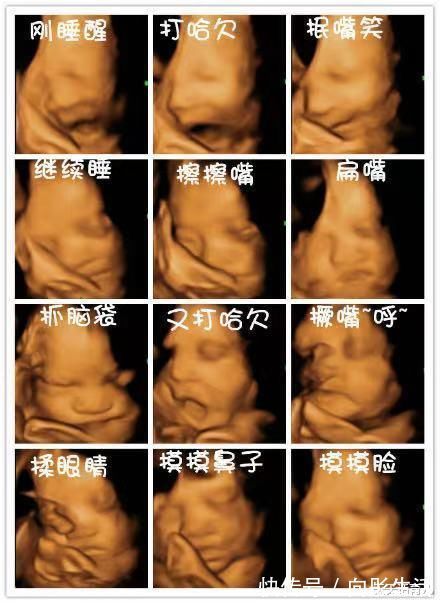

留下珍贵孕期纪念

四维彩超可对胎儿特定体表进行清晰检查,可将检查的整个过程刻录成光盘,将宝宝在宫内的特定部位的动作记录下来,如吐舌头、微笑、皱眉头、肢体动作等,是独一无二的孕期纪念,也是送给未来宝宝的珍贵礼物。